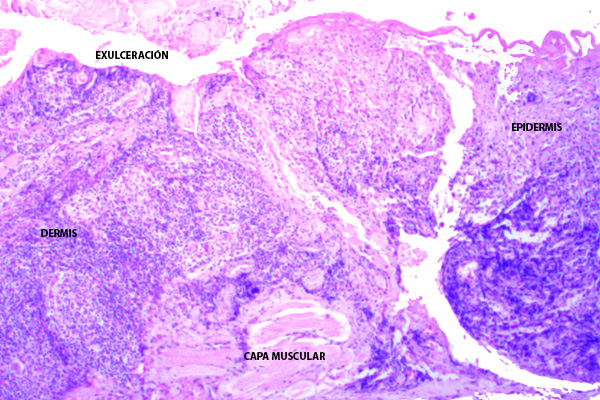

La leishmaniasis cutánea en el párpado comparte las características histológicas generales de la forma cutánea, pero su localización periocular (cercana a estructuras sensibles) la hace particularmente importante. La histopatología de la leishmaniasis cutánea varía según la fase evolutiva de la lesión y la respuesta inmunológica del paciente.

Se aprecian cambios cónsonos con una dermatitis granulomatosa crónica con ulceración.

La característica más notable es un infiltrado inflamatorio denso y difuso que ocupa la dermis.

El infiltrado inflamatorio es intenso, a menudo respetando un «espacio» debajo de la epidermis (la zona de Grenz). Sin embargo, como en este caso puede estar ausente por la extensa ulceración.

Los microabscesos pueden alcanzar las capas más profundas del párpado, disecando las fibras musculares estriadas del orbicular de los párpados (FM).